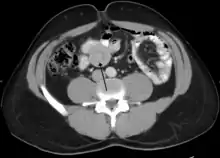

Small intestinal invagination on computed tomography

An intussusception is often suspected based on history and physical exam, including observation of Dance's sign. A digital rectal examination is particularly helpful in children, as part of the intussusceptum may be felt by the finger. A definite diagnosis often requires confirmation by diagnostic imaging modalities. Ultrasound is the imaging modality of choice for diagnosis and exclusion of intussusception, due to its high accuracy and lack of radiation. The appearance of target sign (also called "doughnut sign" on a sonograph, usually around 3 cm in diameter, confirms the diagnosis. The image seen on transverse sonography or computed tomography is that of a doughnut shape, created by the hyperechoic central core of bowel and mesentery surrounded by the hypoechoic outer edematous bowel.[11] In longitudinal imaging, intussusception resembles a sandwich.[11] It is also called "pseudokidney" sign because hyperechoic tubular centre is covered by a hypoechoic rim producing a kidney-like appearance.[12]